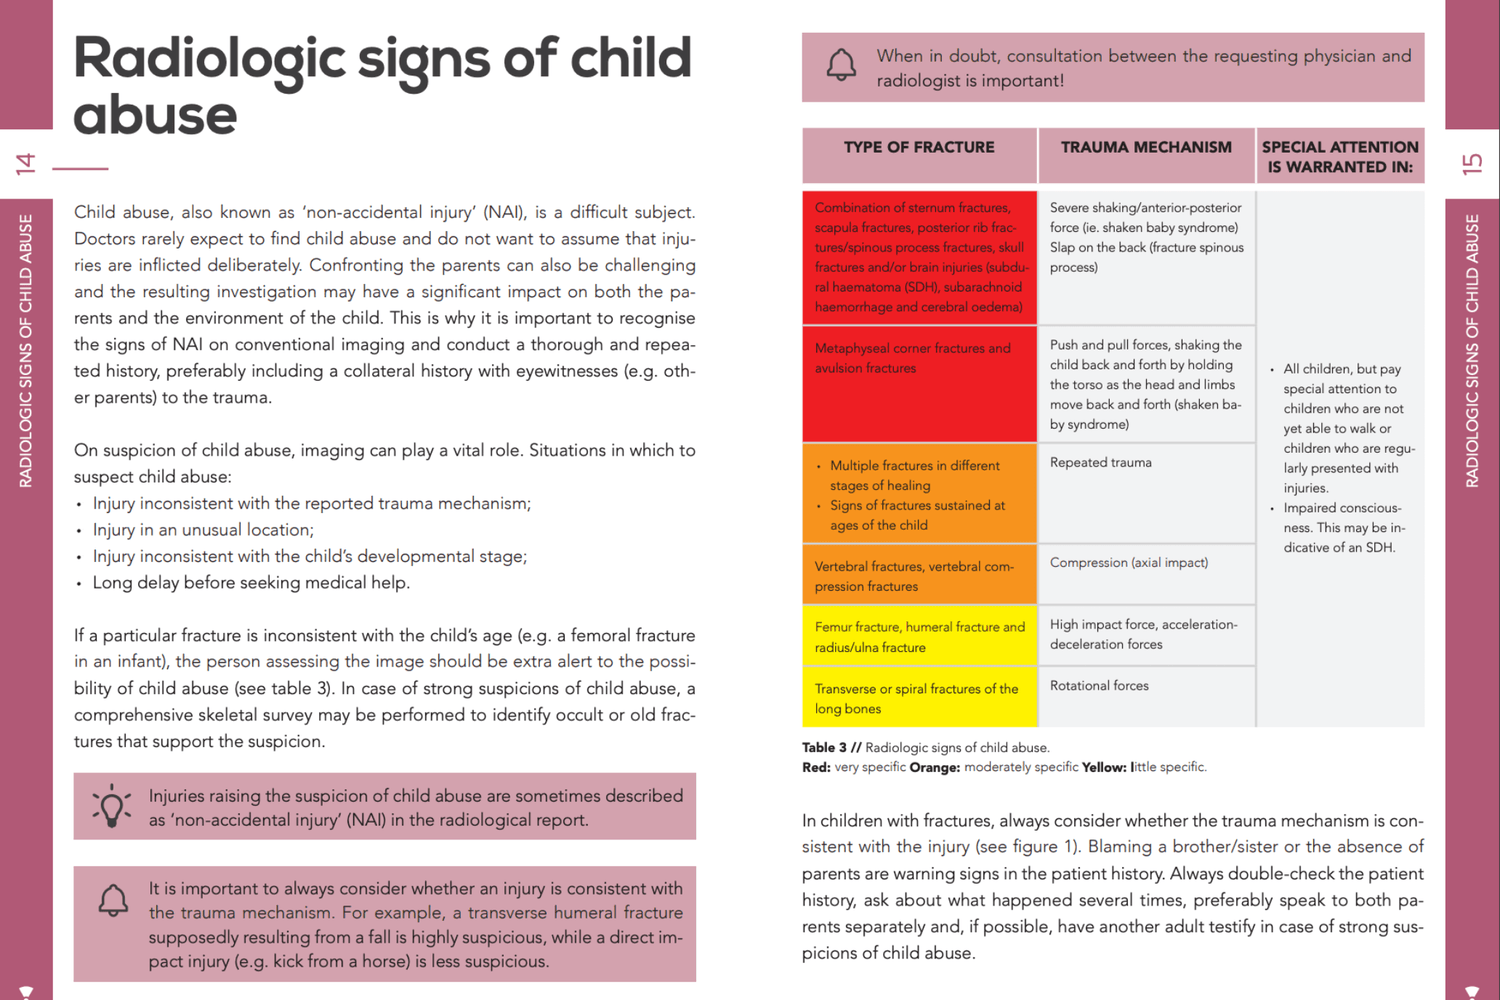

Indicated imaging in intracranial haemorrhage

Tables to present information clearly